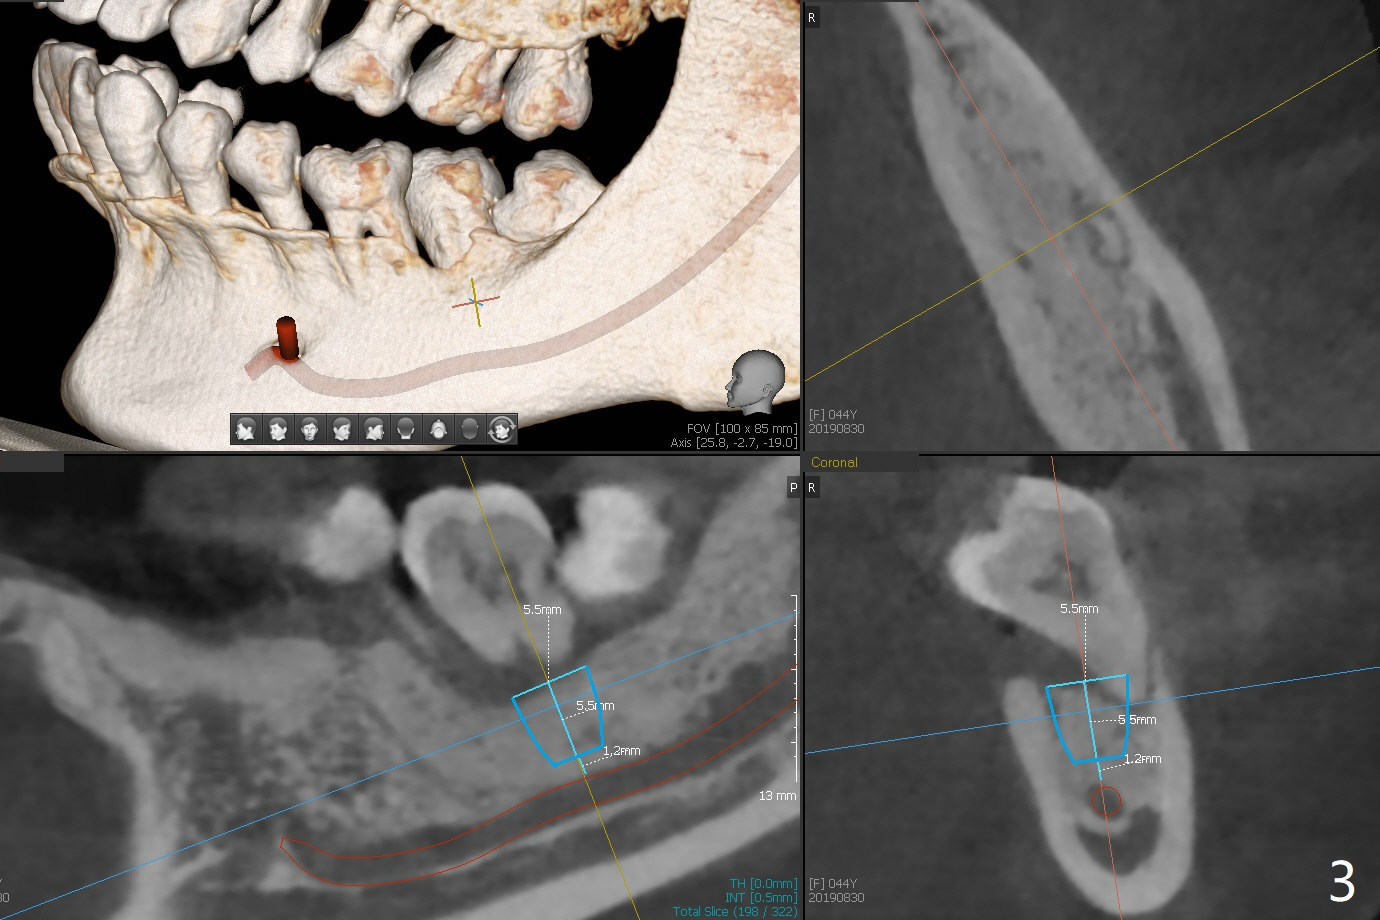

A 44-year-old woman has severe chronic periodontitis. The tooth #18 is nonsalvageable (Fig.1). To avoid distal end guide, do not remove the 3rd molar in the lab. While a 5x7.3 mm implant is long for the site (Fig.2), a 5.5x5.5 mm one seems to be a better option (Fig.3). The latter could be 1 mm more coronal. The last drill (5.0 mm) and cortical tap will be used free hand. #17 will be extracted after implantation. Since the patient is reluctant to have #16 to be extracted, place #18 implant ~ 1-2 mm more distal so that the implant crown will have some occlusal contact with #16. Prepare IS extra wide kit. Or use a 8/7 mm trephine bur to harvest cortical bone from the ramus. Drill a hole for fixation screw before removing the onlay graft. Keep the 3rd molar if possible. Prepare Tatum spacers to measure the size of #18 socket opening. In fact, the lab is able to place a 5x7.3 mm implant with 2 thread exposure buccal. Prepare sticky bone and PRFx2 to prevent periimplantitis. Soak one O-ring in case of having to extend osteotomy by .5 mm (next longer drill (1.5 mm) - 1 mm (O-ring)). For socket shield at #18 (Fig.6 *), section the tooth horizontal with a new surgical fissure bur (Fig.4 black area), use an end-cutting bur to remove buccal edge of the root (Fig.5 red area) and finally remove the lingual portion of the root (Fig.6 pink). Insert 4.5x10 mm dummy implant to determine whether the final implant 5x7.3 mm (bottom of the 1st line) will probably contact the shield. Buccal view of the lingually inclined 2nd molar (Fig.7). After removal of the crown of the 2nd molar (Fig.8 occlusal view), the lingual portion of the root is resected (Fig.9 black area). CT coronal sections show socket shield formation (Fig.10,11).

Lower Molar Immediate Implant, Prevent Molar Periimplantitis (Protocols, Table), Trajectory II, No Antibiotic Xin Wei, DDS, PhD, MS 1st edition 08/30/2019, last revision 02/02/2020